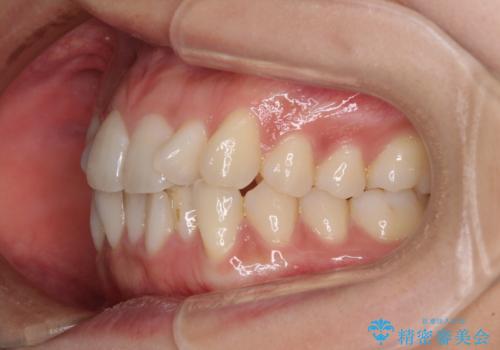

- 上下前歯のねじれを気にして来院された患者様です。

ワイヤー矯正でもマウスピース矯正でも対応可能でしたが、マウスピース矯正の自己管理が面倒であること、上顎前歯の捻転が著しいことから、ワイヤー矯正での治療を希望されました。